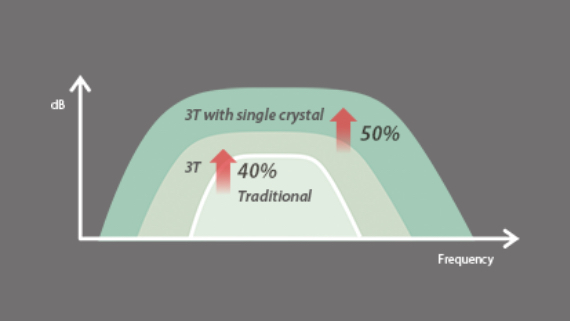

Echo Boost yang canggih

Terobosan beruntun Mindray untuk visualisasi gambar ultrasound terbaik.